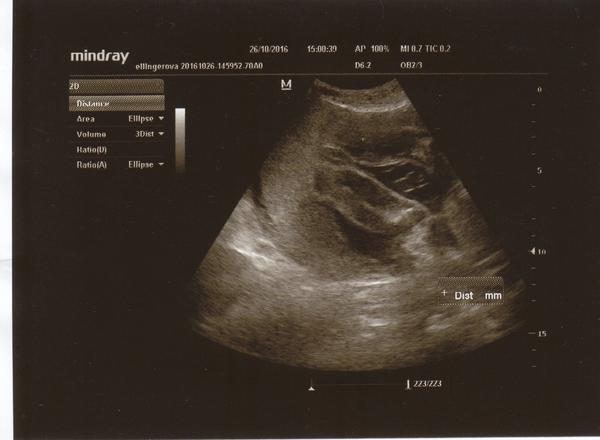

Je to holčička nebo chlapeček? Foto ultrazvuku

@ellilenka mne to prijde jako kavove zrno,kulicky by byly spis vic vepredu.

Doktor jen řekl, že tam pindíka nevidí. Ale jestli je to kluk nebo holka vyloženě neřekl. Nemůžu si pomoct, ale cítím se na kluka. Je to úplně jiné těhotenství, než s první dcerou. Prostě pravý opak všeho. Tady mi jde o to, že jsem viděla dva skoro totožné ultrazvuky, tvrdily také, že je tam jasné kávové zrno a oni se z toho vyklubali kluci jako buci ☺

Tak díky za info já na to koukala pořádně a opravdu je to pupeční šňůra a já se už těšila že by to mohla být druhá holčička :D tak hold příště :D